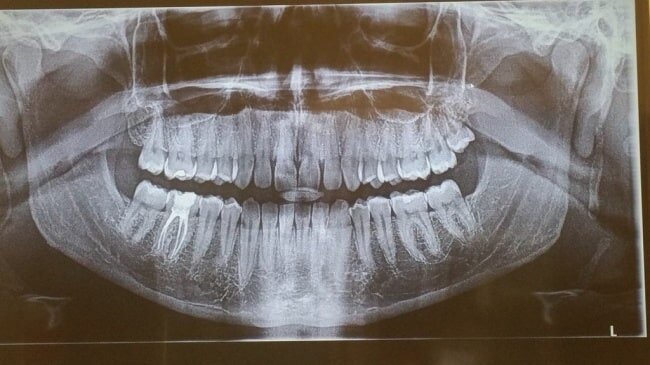

16. Отсутствие зубов мудрости

20 % людей рождается без зубов мудрости, это считается вариантом нормы. В каких-то народах такое явление встречается чаще, а в каких-то реже. Например, отсутствие зубов мудрости замечено почти у 100 % коренных народов Мексики, чего практически не бывает у тасманийцев. Такая разница связана с геном PAX9 и, скорее всего, с рядом других генов.